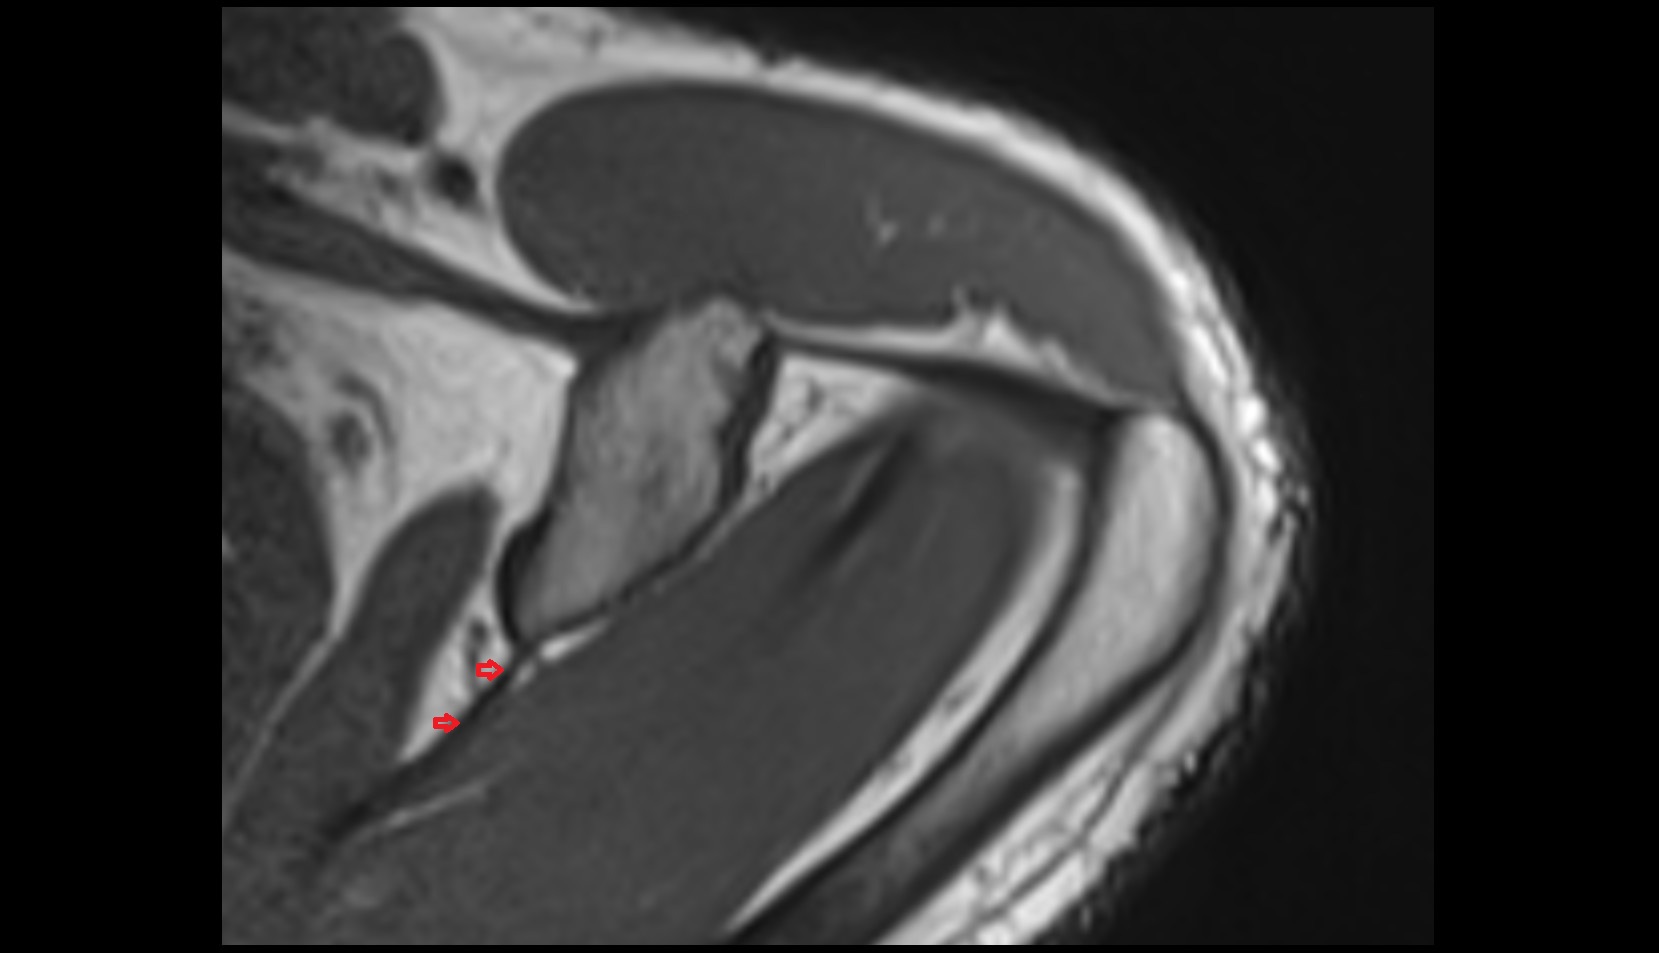

- Articular disc of temporomandibular joint

- Articular eminence

- Attachment of inferior head of lateral pterygoid muscle

- Attachment of superior head of lateral pterygoid muscle

- Intermediate zone of articular disc

- Superior retrodiscal layer

- Superior synovial membrane of temporomandibular joint

- Temporomandibular joint

- Mandibular condyle

- Superior head of lateral pterygoid muscle

- Inferior head of lateral pterygoid muscle